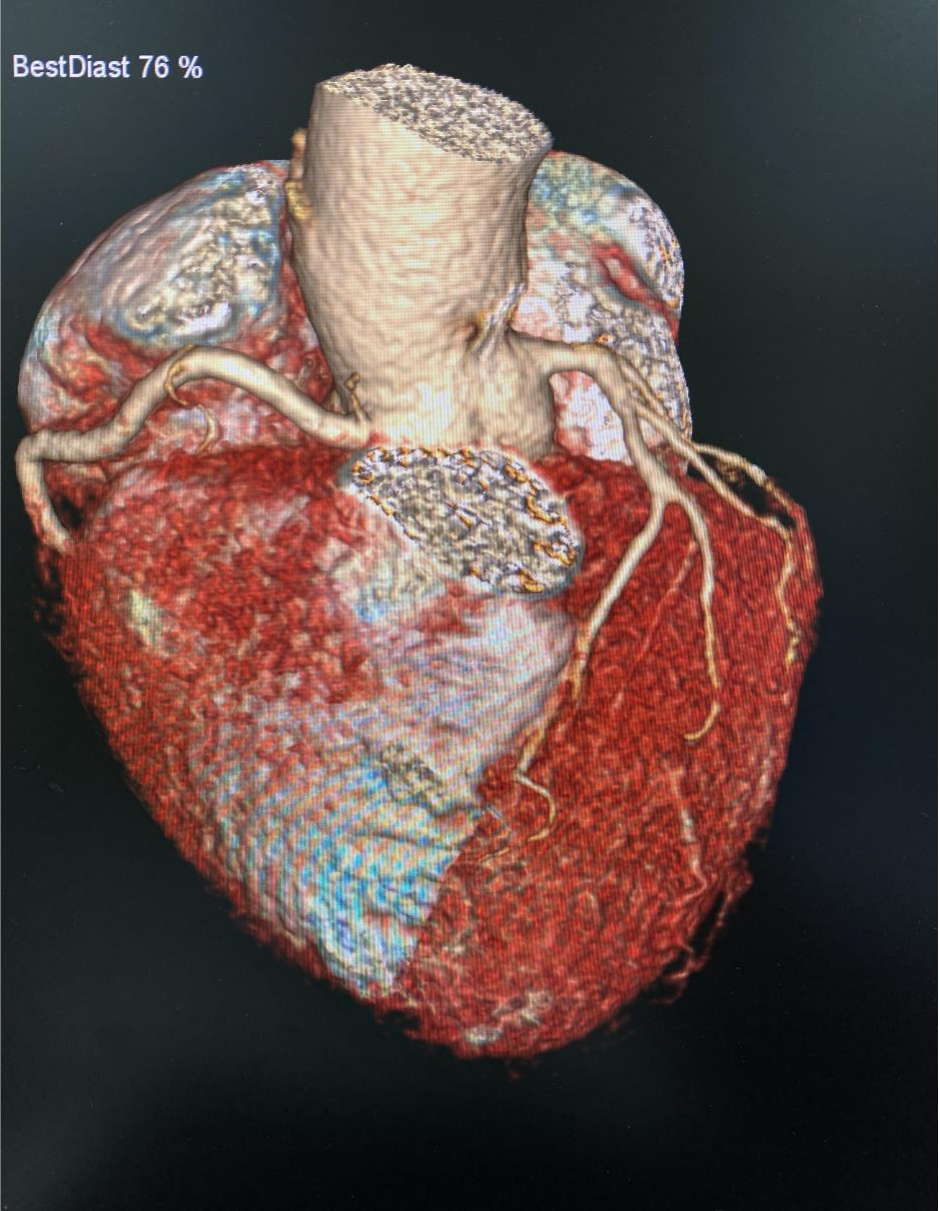

SOMATOM Drive光子双源CT是西门子双源CT中的高档机器,在继承了前三代双源CT的各项先进技术的基础上,创新性地在精准影像、安全影像和智能影像方面进行了变革,引领CT发展的新纪元。Drive CT具有快速、精准、安全的特点,在心脏冠脉检查、肿瘤筛查、超低剂量体检、低对比剂应用和大范围血管检查等方面具有显著优势。

该设备具备强大的后处理工作站,可以自动预处理各类图像,还具有常规及标准高级三维后处理及三维阅片功能,使得图像扫描、技术处理等更加快捷、高效,同时也为诊断和临床医生提供了极大的方便。

医学影像科在李涛、王鹏两位主任的积极领导下,先后开展全身各部位、多部位联合扫描及强化,CT增强扫描开展了冠状动脉CTA、肺动脉CTA、头颈部血管CTA、胸腹主动脉CTA、下肢动脉CTA等多项新技术、新项目。

在开展新技术新项目不久后,便有多个科室及病源需求,李涛主任积极联系各临床科室,了解影像检查需求,王鹏主任积极协调科室新技术新项目工作。近日,医学影像科开展首例冠状动脉造影CT检查时,令科室医技人员记忆犹新的是这位心率高且不稳定的患者,担心心率问题会影响检查,但是当他得知用双源CT进行检查,就算在心率不齐情况下也不会影响图像及诊断时,悬着的心终于放下了。护士长王姗姗为病人穿刺静脉留置针并安装连接高压注射器后,耐心嘱咐病人,平抚病人的情绪。

影像技师张锐准确的选择好扫描条件,计算好造影剂剂量、注射速率等方案后进行规范扫描,扫描完成,各支血管显示清晰,完成处理后传输到报告系统。

VR

完成检查后,两位主任对图像、报告进行综合评价及审核。各项流程顺利,项目开展完好,填补我院血管强化检查领域空白,为我院医学影像发展开启了新的篇章!